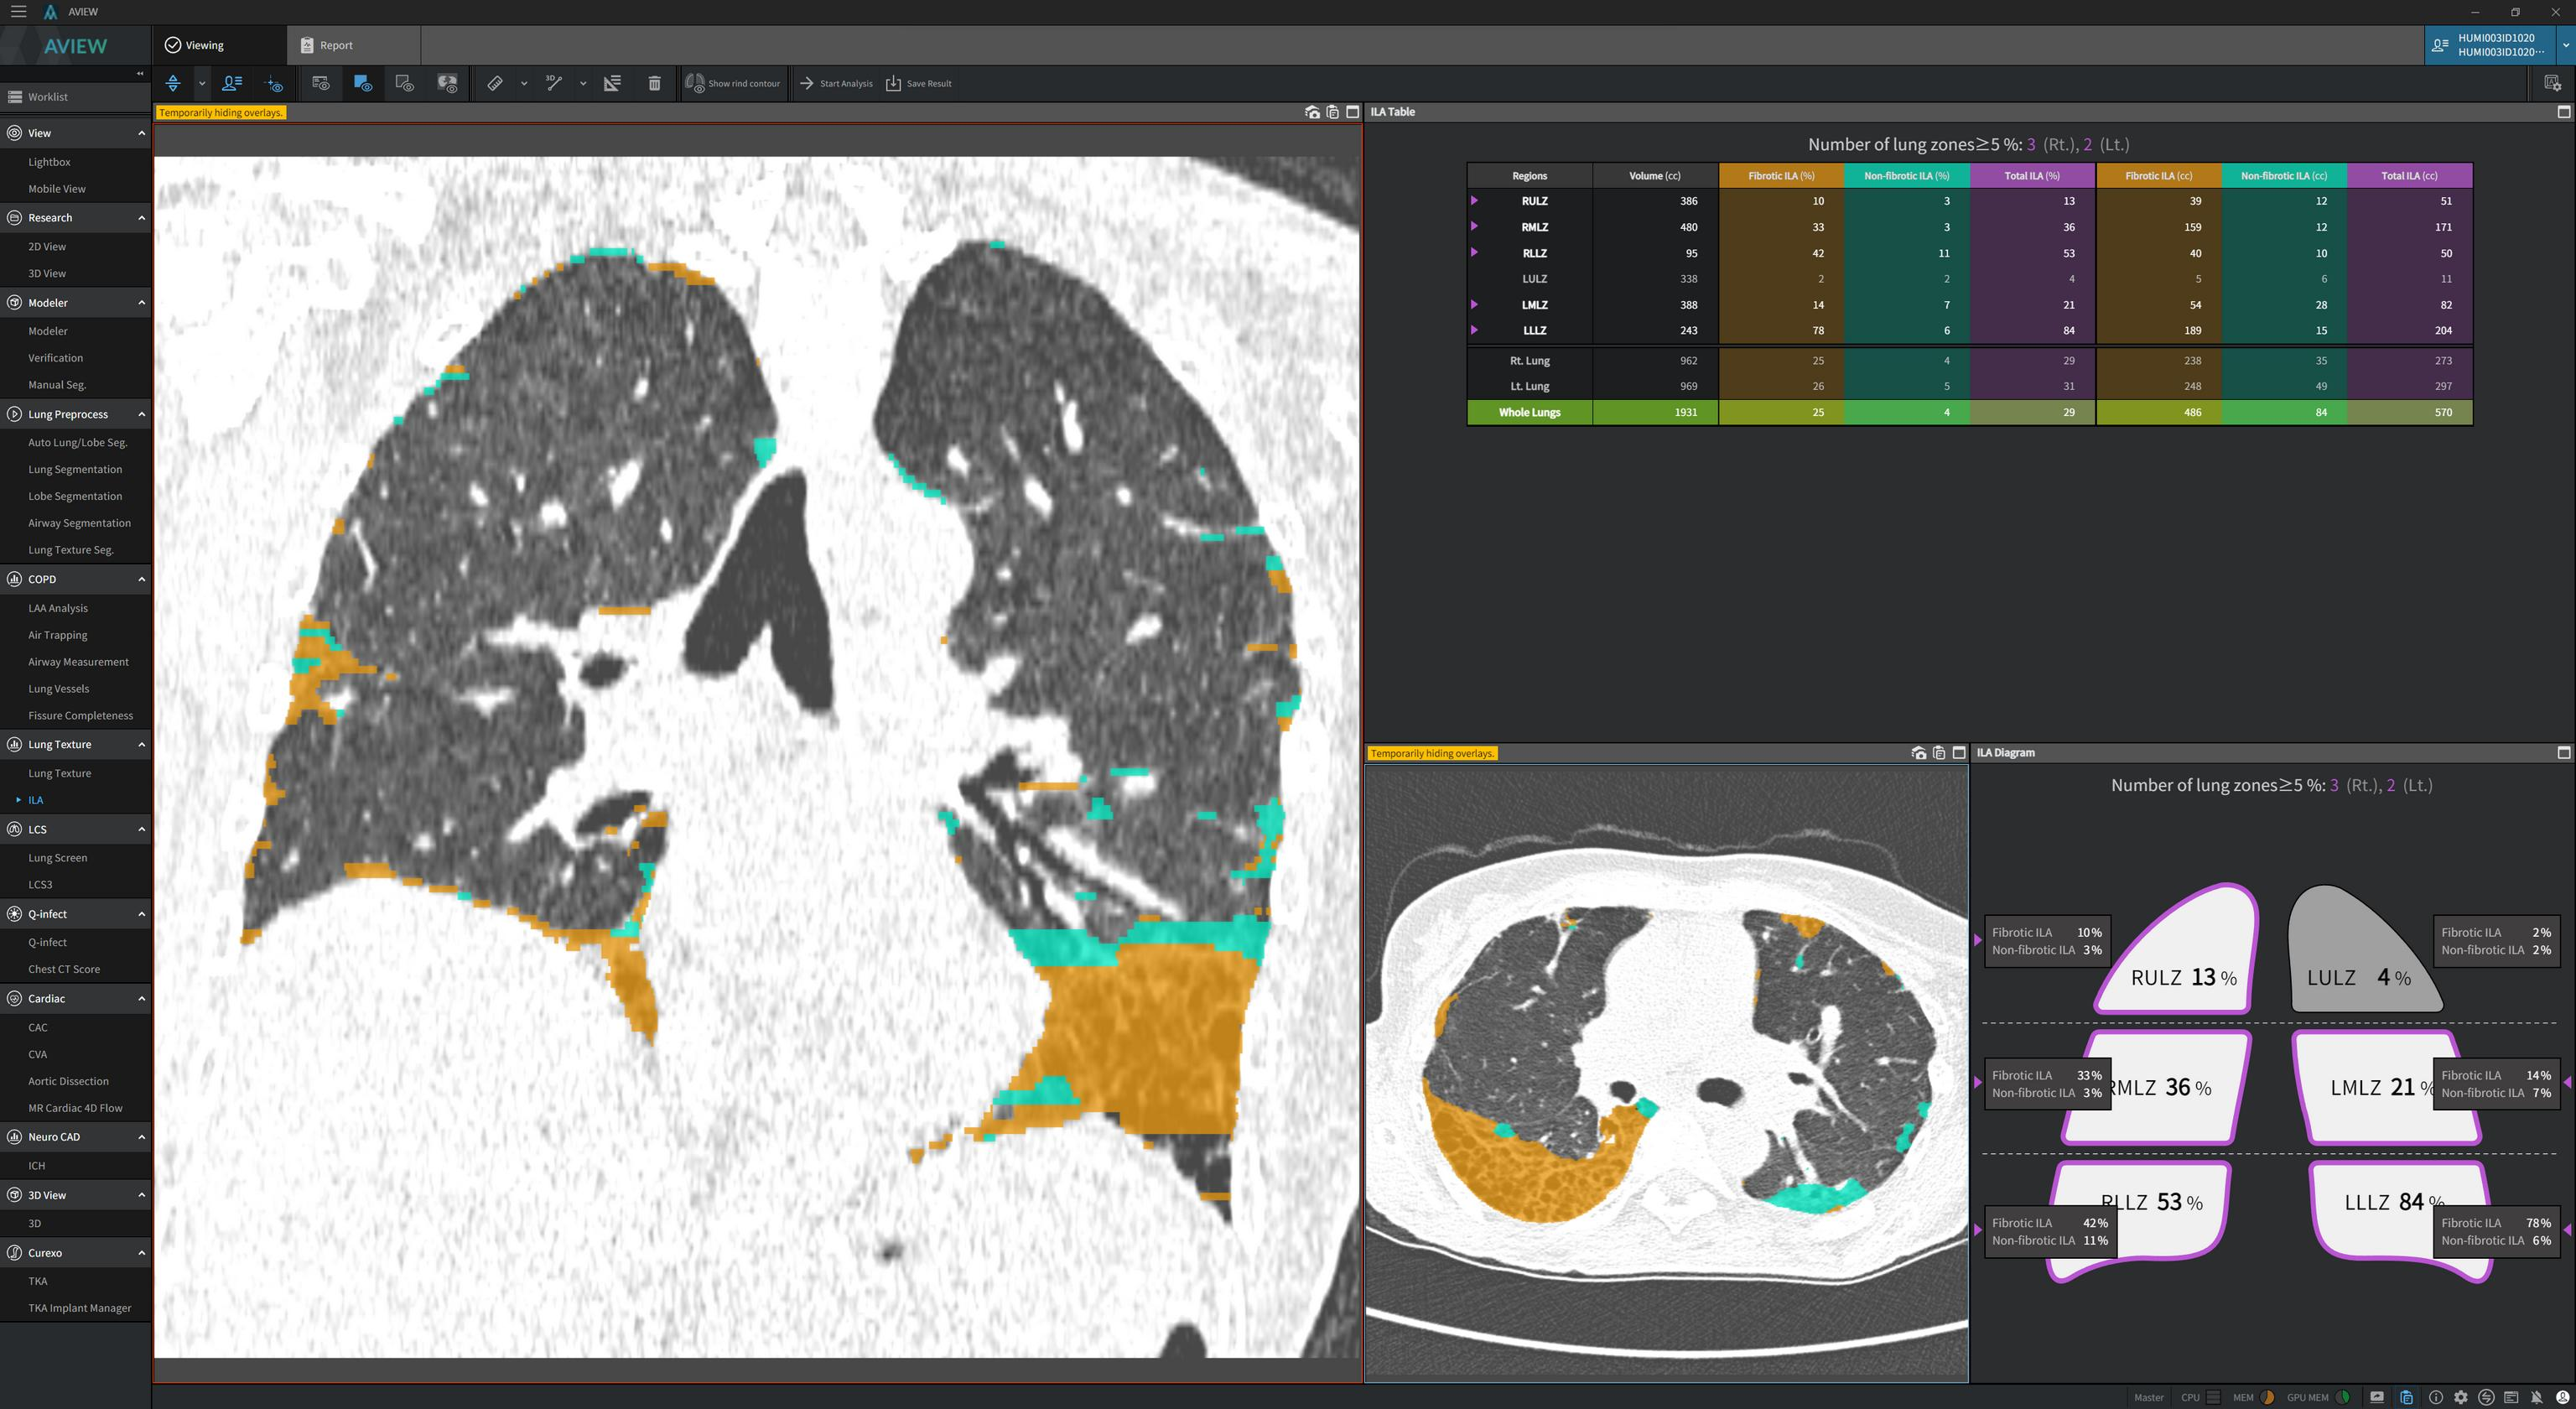

그런데 5%라는 기준은 사실 인간이 정량적으로 눈으로 측정하기는 어렵습니다. 영상의학과 의사의 주관적 판단에 의거한 기준이기 때문에 Quantitative CT (QCT)가 필요하게 되고 상용화된 제품으로는 한국의 코어라인소프트의 AVIEW 제품이 이러한 정량화를 해줍니다. 아래 사진처럼, abnormal lung area를 fibrotic ILA와 non-fibrotic ILA로 분할하고 lung zone에 따라 5% 이상 침범한 영역이 어디에 있는지를 모식도로 나타내 줍니다.